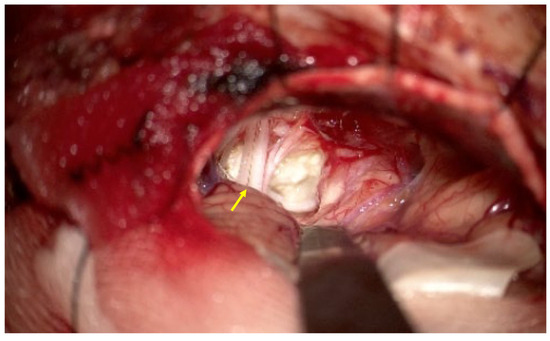

The patient was admitted for elective surgery several weeks after the initial outpatient evaluation. On preoperative examination, she was alert and oriented but exhibited left-sided facial hypesthesia and severe sensorineural hearing loss. Prior to surgical intervention, a comprehensive systemic evaluation was performed to exclude metastatic disease. Whole-body imaging, including 18F-FDG positron emission tomography/computed tomography, revealed no evidence of a primary extracranial malignancy, and otolaryngologic examination, including endoscopic evaluation of the upper aerodigestive tract, revealed no suspicious lesions. A left retrosigmoid suboccipital craniotomy was performed with image-guided navigation. Upon opening the dura, the surgical field revealed marked displacement of the sixth, seventh, eighth, and lower cranial nerves (Figure 2). The lesion consisted of two distinct components. The first was a typical epidermoid cyst—a soft, pearly white, avascular mass—which was easily debulked via suction. Beneath this layer, however, a firm, vascularized solid mass was identified, extending into the internal auditory canal (IAC) and adhering tightly to the brainstem and vestibulocochlear nerve complex. This solid component exhibited frequent contact bleeding and lacked a clear dissection plane, initially mimicking a hemorrhagic vestibular schwannoma. Intraoperative frozen-section analysis confirmed the presence of malignant cells with squamous differentiation. Given the tumor’s firm adherence to critical neurovascular structures and the high risk of permanent neurological deficit, a decision was made to perform a maximal safe subtotal resection rather than risking gross total removal.

Figure 2.

Intraoperative view of the left cerebellopontine angle lesion obtained via a retrosigmoid approach. The exposed tumor demonstrates the characteristic pearly white, flaky appearance consistent with an epidermoid cyst component. Adjacent cranial nerve bundles are visibly displaced and stretched over the tumor surface (arrow), reflecting the local mass effect within the cerebellopontine angle cistern. Although the superficial component showed benign macroscopic features, the deeper portion exhibited firm adhesion to the brainstem, corresponding to the malignant component identified on histopathologic examination.